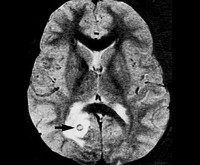

• Жидкостная. По центру образования находится жидкость. Жидкостная туберкулома томографически не отличается от абсцесса головного мозга. Гипо-, изоинтенсивна в режимах Т1, Т2, контрастируется как узкое кольцо. Отличается высокой интенсивностью сигнала на диффузно-взвешенных изображениях.

• МРТ головного мозга. Рекомендовано тщательное комплексное исследование с использованием Т1/Т2 режимов, диффузионно-взвешенных изображений, МР-спектроскопии. В пользу туберкуломы говорит небольшой перифокальный отёк, наличие оболочки, кольцевидное контрастирование.